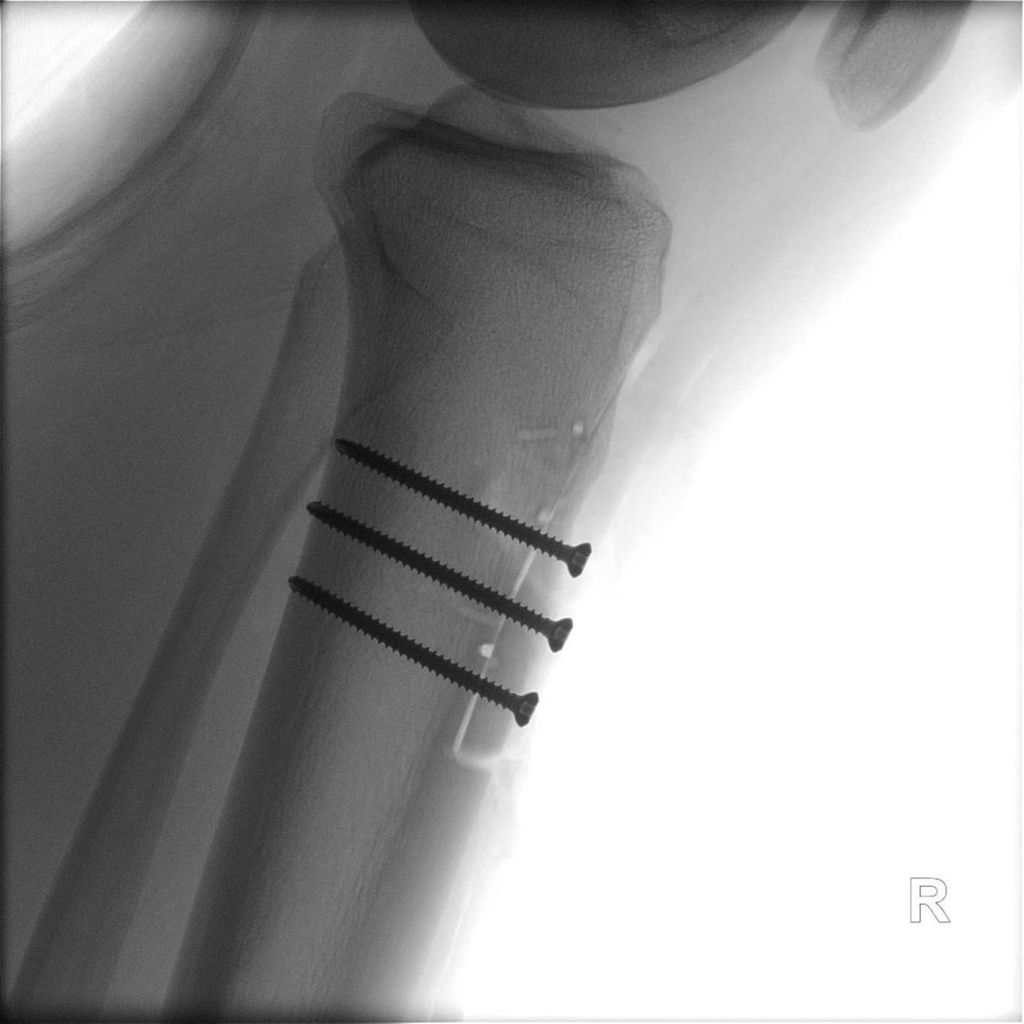

17-jähriger Patient mit wiederkehrenden Patellaluxationen

Aufgrund eines erhöhten Caton-Deschamps-Index von >1,2 erfolgten die Tuberositasdistalisierung und die MPFL-Plastik mit der Gracillissehne (Abb. 2 und 3). Ca. 4 Wochen nach dem operativen Eingriff stürzte der Patient auf das rechte Kniegelenk mit Mehrfragmentbruch des Tuberositasfragments (Abb. 4). Die neuerliche Fixierung erfolgte mittels 3,5mm-Drittelrohrverplattung sowie, wegen des Mehrfragmentbruches im proximalen Bereich, mittels Durchflechtungsnaht und Knochenankern (Abb. 5).

Abb. 5: Intraoperatives Bild nach Verplattung und Zügelung mittels Durchflechtungsnaht und Knochenankern